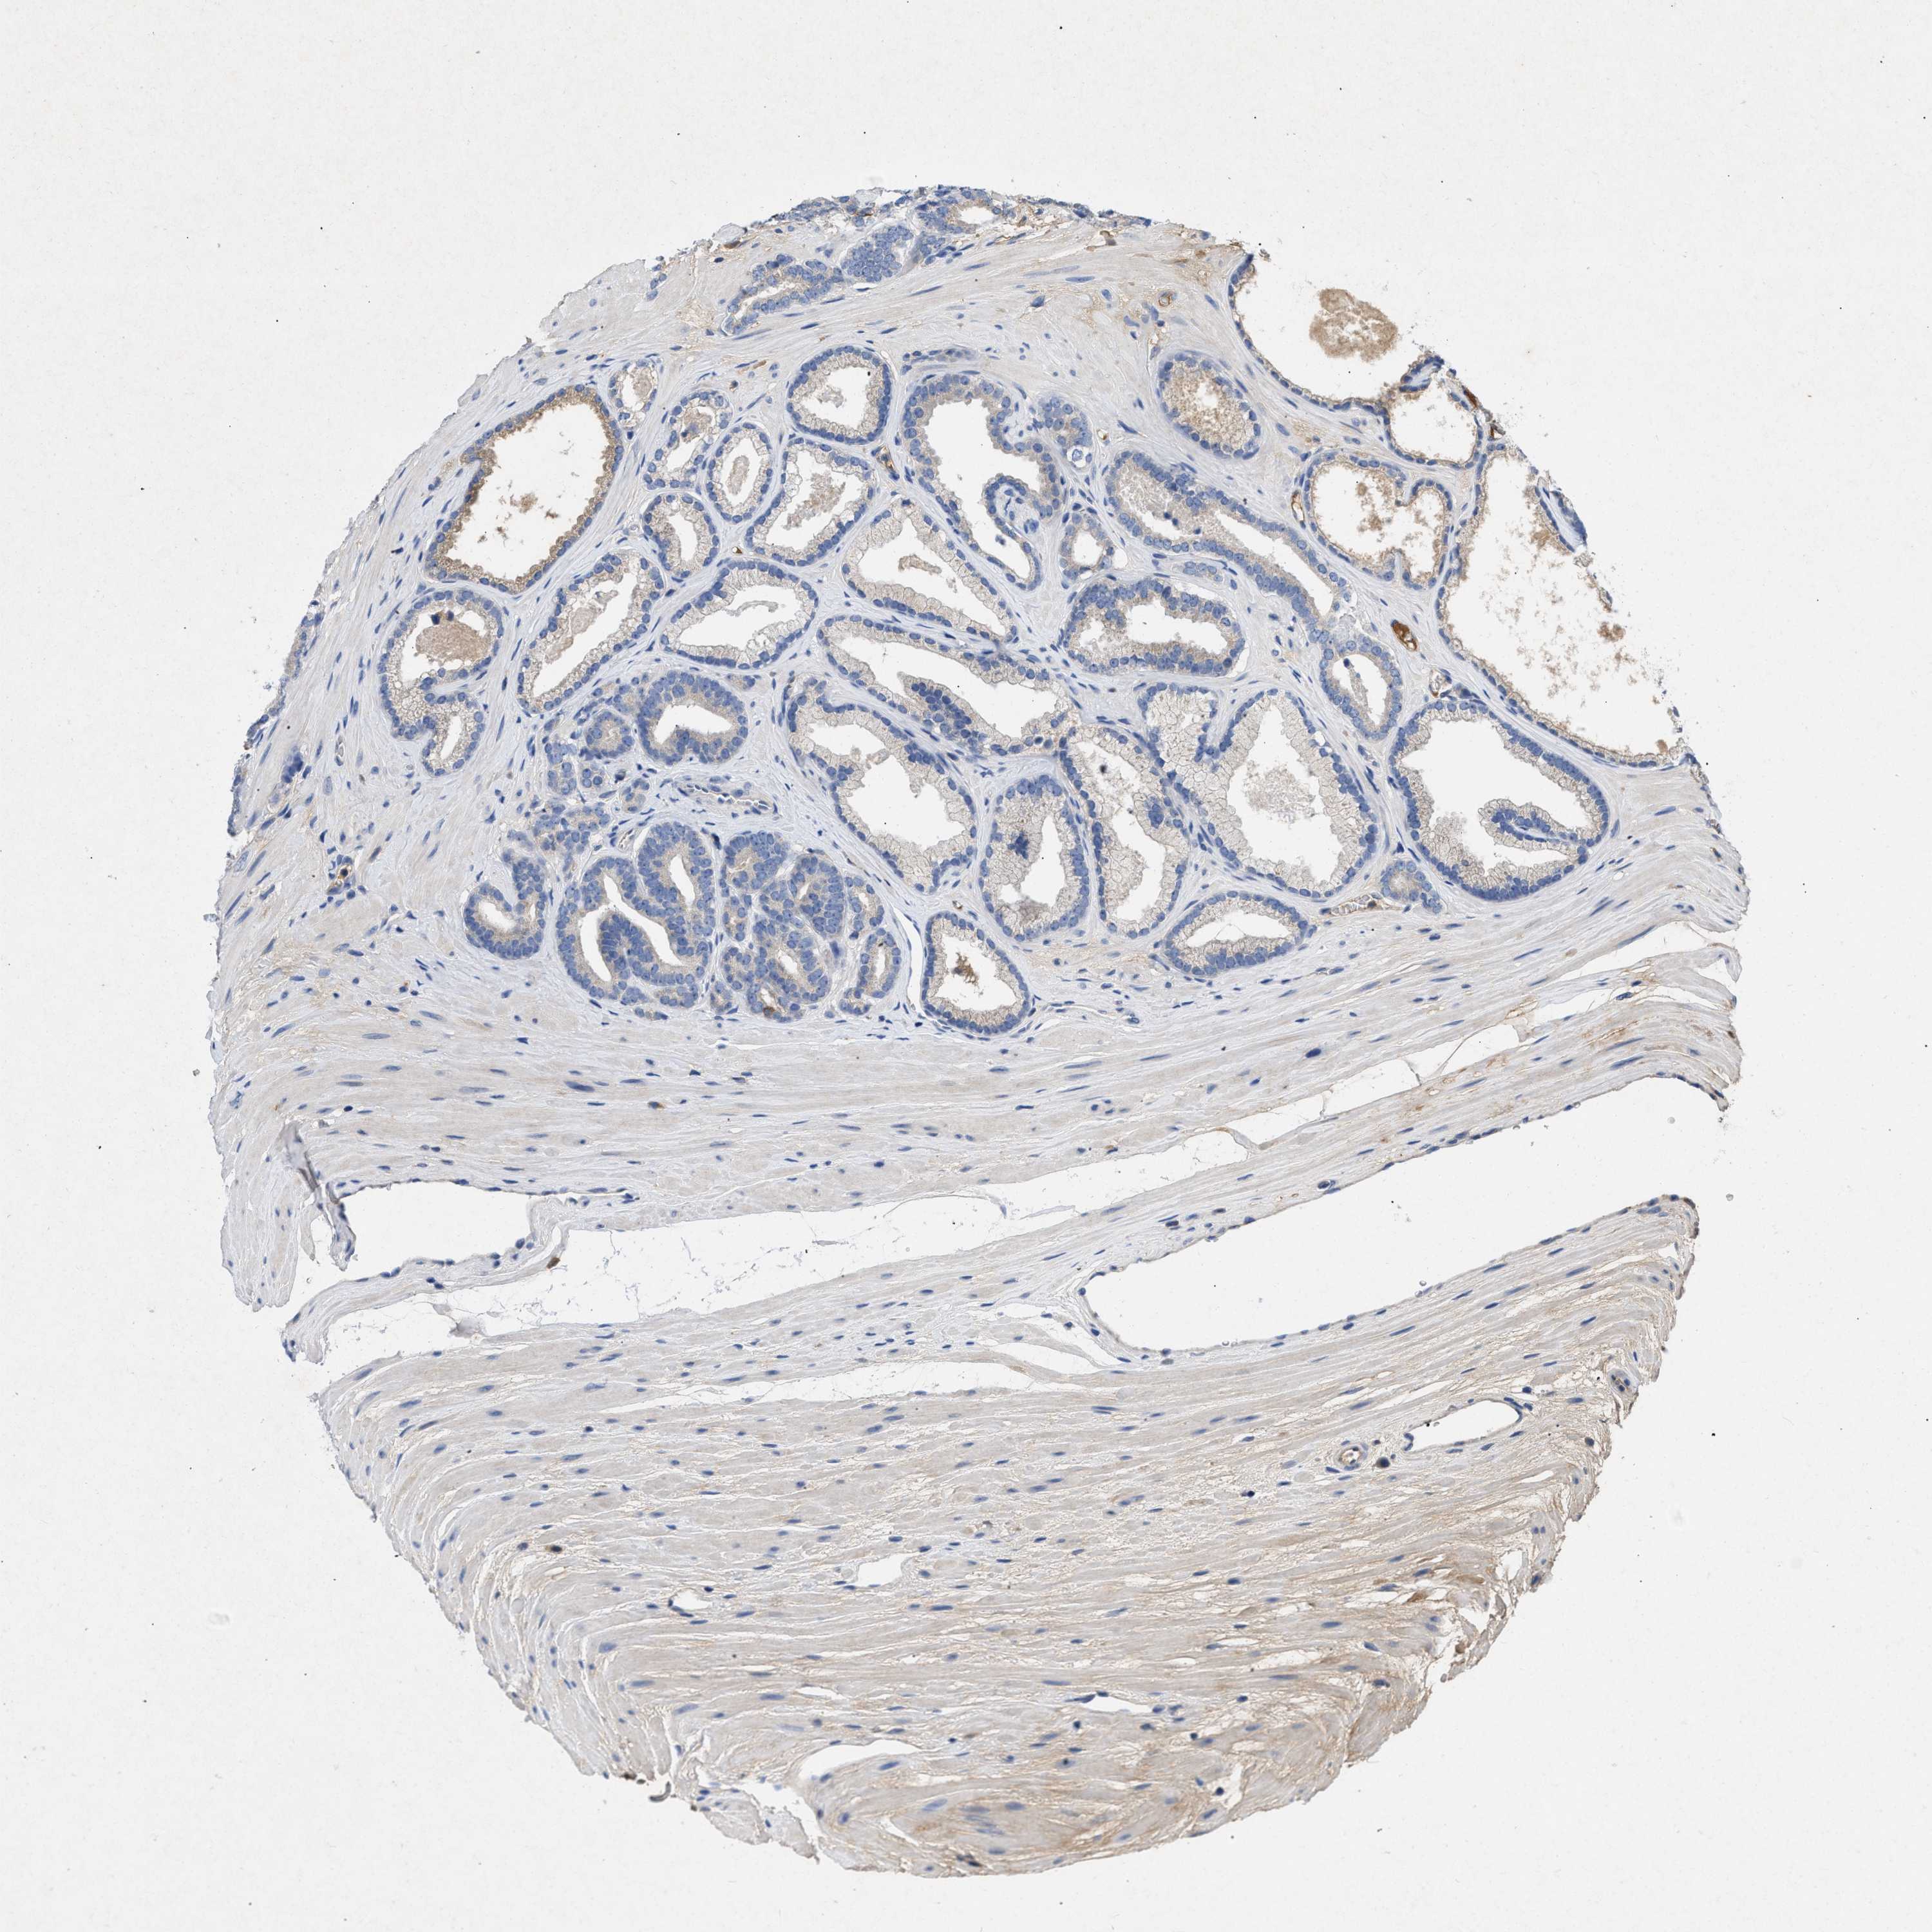

PROSTATE CANCER - Protein expressioni

A mouse-over function shows sample information and annotation data. Click on an image to view it in a full screen mode. Samples can be filtered based on level of antibody staining by selecting one or several of the following categories: high, medium, low and not detected. The assay and annotation is described here.

Note that samples used for immunohistochemistry by the Human Protein Atlas do not correspond to samples in the TCGA dataset.

Antibody stainingi

Antibody staining in the annotated cell types in the current human tissue is reported as not detected, low, medium, or high, based on conventional immunohistochemistry profiling in selected tissues. This score is based on the combination of the staining intensity and fraction of stained cells.

Each image is clickable and will lead to virtual microscopy that enables deeper exploration of all samples and also displays staining intensity scores, fraction scores and subcellular localization as well as patient and tissue information for each sample.

Antibody CAB018751

Antibody CAB034411

Staining

High

Medium

Low

Not detected

Intensity

Strong

Moderate

Weak

Negative

Quantity

>75%

75%-25%

<25%

None

Location

Nuclear

Cytoplasmic/membranous

Cytoplasmic/membranous,nuclear

Adenocarcinoma, High grade

Adenocarcinoma, Low grade